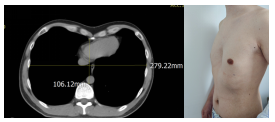

近日,清华大学附属垂杨柳医院胸外科成功为一位青年男性患者实施漏斗胸矫正手术。该患者男性32岁,自幼发现前胸壁凹陷,无不适症状,因此未治疗。最近9个月患者间断出现胸闷、心悸等不舒服,并且自觉胸壁凹陷明显,经过多方打听,最后前来我科就诊。查体可见前胸壁凹陷,两侧胸壁向内收缩塌陷,左右胸廓对称,最深处位于“心口窝”上方,脊柱对称无侧弯。入院后科室经过详细术前讨论,考虑患者漏斗胸加重,出现胸闷、心悸等不适,并且畸形影响美观,对患者造成心理不适,同时患者本人手术意愿强烈,因此我们于2025年8月14日在全麻下给患者实施了微创胸腔镜漏斗胸矫正术(NUSS手术),手术历时2小时,过程顺利。于胸腔镜引导下精准置入矫形钢板,胸骨抬举满意,胸廓外形即刻得到改善。术后未放置引流管,切口采用美容缝合,并予镇痛、雾化等综合治疗,患者恢复迅速。

手术前CT及胸部照片